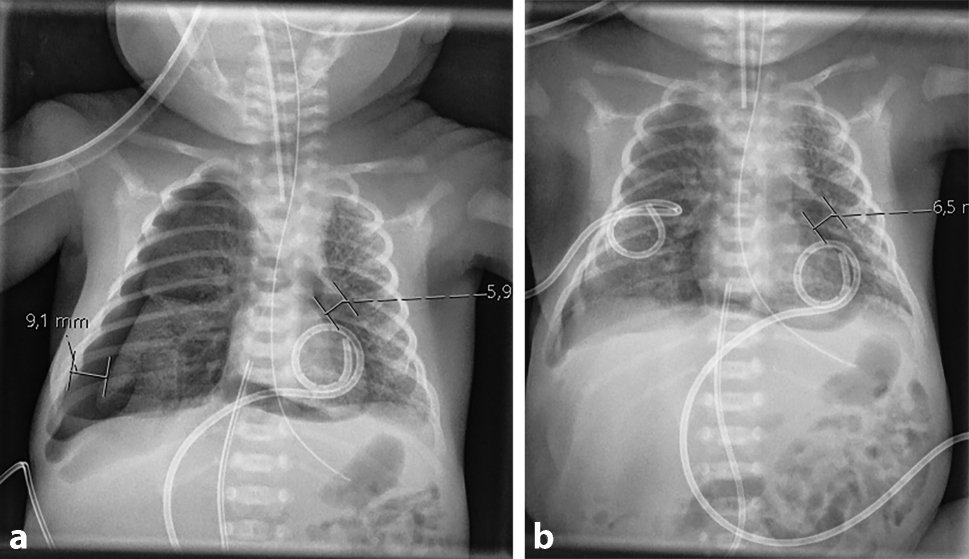

The infant was given two doses of surfactant because of severe respiratory distress syndrome and due to worsening respiratory function, conventional mechanical ventilation was switched to high frequency oscillatory ventilation. On day 2 of life, an echocardiography was performed for PDA (Patent ductus arteriosus) assessment, demonstrating circular air entrapment surrounding the infant’s heart (Video 1). On chest X‑ray, suspected pneumopericardium was confirmed (Fig. 1a), and a pericardial tube was inserted with continuous drainage for 3 days (Fig. 1b). The following day the neonate developed right-sided pneumothorax (Fig. 2a), which mandated the insertion of a chest drain (Fig. 2b).

Fig. 1

a Chest X-ray demonstrating circular pneumopericardium, b Chest X-ray after insertion of pericardial tube (pigtail)